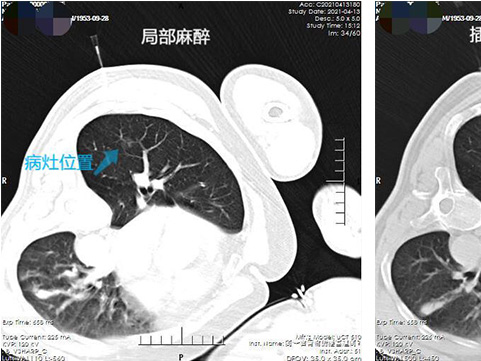

肺結(jié)節(jié)治療不開胸 射頻消融術(shù)治療效果好

近些年肺結(jié)節(jié)患者數(shù)量逐年增加,每當(dāng)拿到體檢報告,各種肺部結(jié)節(jié)、磨玻璃結(jié)節(jié)的字樣讓人看了非常害怕,為滿足患者就診需求,錦州市中心醫(yī)院增設(shè)了肺結(jié)節(jié)門診,為患者答疑解難。